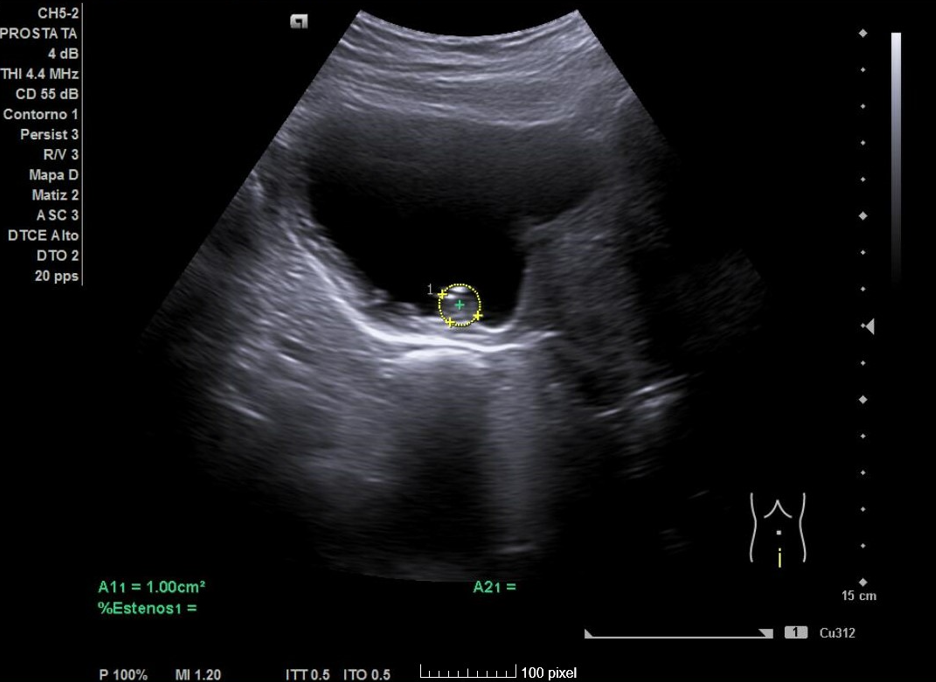

Primera ecografía: Riñón derecho de 9,6 cm, izquierdo de 9,5 cm, escoestructura y morfología normales. Vejiga con aumento de grosor de pared, residuo premiccional y posmiccional similares en torno a 350 cc (probable vejiga de lucha). Pólipo vesical a expensas de pared inferior izquierda de 18,5 x 8,7 mm. Jet ureteral bilateral conservado. Próstata de 110 cc. Se repite ecografía al mes: Pólipo vesical de 14 x 9,7 mm, próstata de 119 cc, vejiga con volumen premiccional 469 ml y posmiccional 400 ml.

• Se comprueba hipertrofia prostática; además, se observa pólipo vesical de etiología no filiada (a descartar neoplasia vesical).